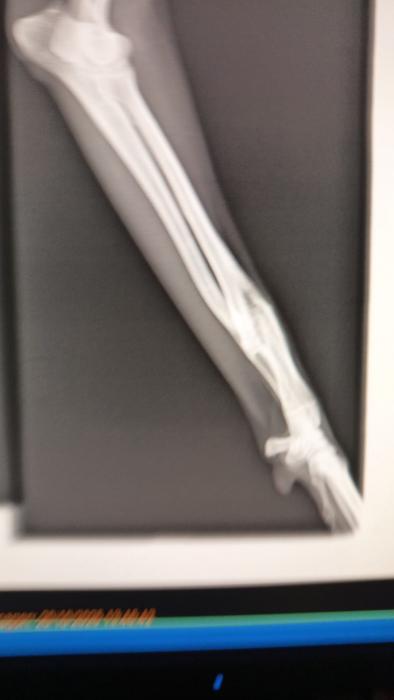

Electra es un deshecho de la caza como muchos otros, es una galguita preciosa, algo tímida pero seguro en un hogar recuperaría rápidamente, se lleva bien con perros y gatos, tiene una expresión muy tierna, seguramente la dejaron por una rotura ya soldada que tiene en su patita delantera, esta pequeña lesión no le impide realizar vida normal y no es necesario operarla.